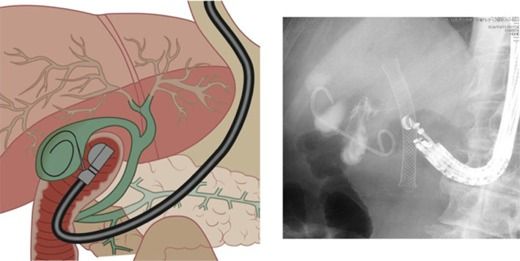

Il dr Claudio Zulli si è laureato con votazione di 110/110 e lode in Medicina e Chirurgia presso la Seconda Università degli Studi di Napoli. Iscritto all’Ordine dei Medici di Salerno con numero 10012, si è specializzato in gastroenterologia con votazione di 50/50 e lode presso l’Università Federico II di Napoli. Opera a Salerno e provincia nell’ambito della gastroenterologia e dell’endoscopia digestiva diagnostica ed operativa avanzata. Nello specifico si è ultra-specializzato nella diagnosi e nel trattamento non invasivo delle malattie del pancreas e delle vie biliari, dei tumori precoci ed avanzati dell'apparato digerente (esofago, stomaco, duodeno, colon, vie biliari, pancreas) e delle malattie infettive ed infiammatorie di stomaco ed intestino. Ha un interesse particolare per la nutrizione e la psicologia, offrendo un inquadramento a 360 gradi del paziente in una visione olistica della persona e della sua patologia.